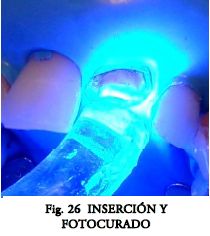

Fotocurar 60 seg. desde la boca del conducto.

Con un poste hígido fotocurar a través del mismo otros 60 seg. Controlar que el poste siempre llegue a la medida.

Se retiran excesos y se fotocura generosamente 60 seg. o más (fig. 26).